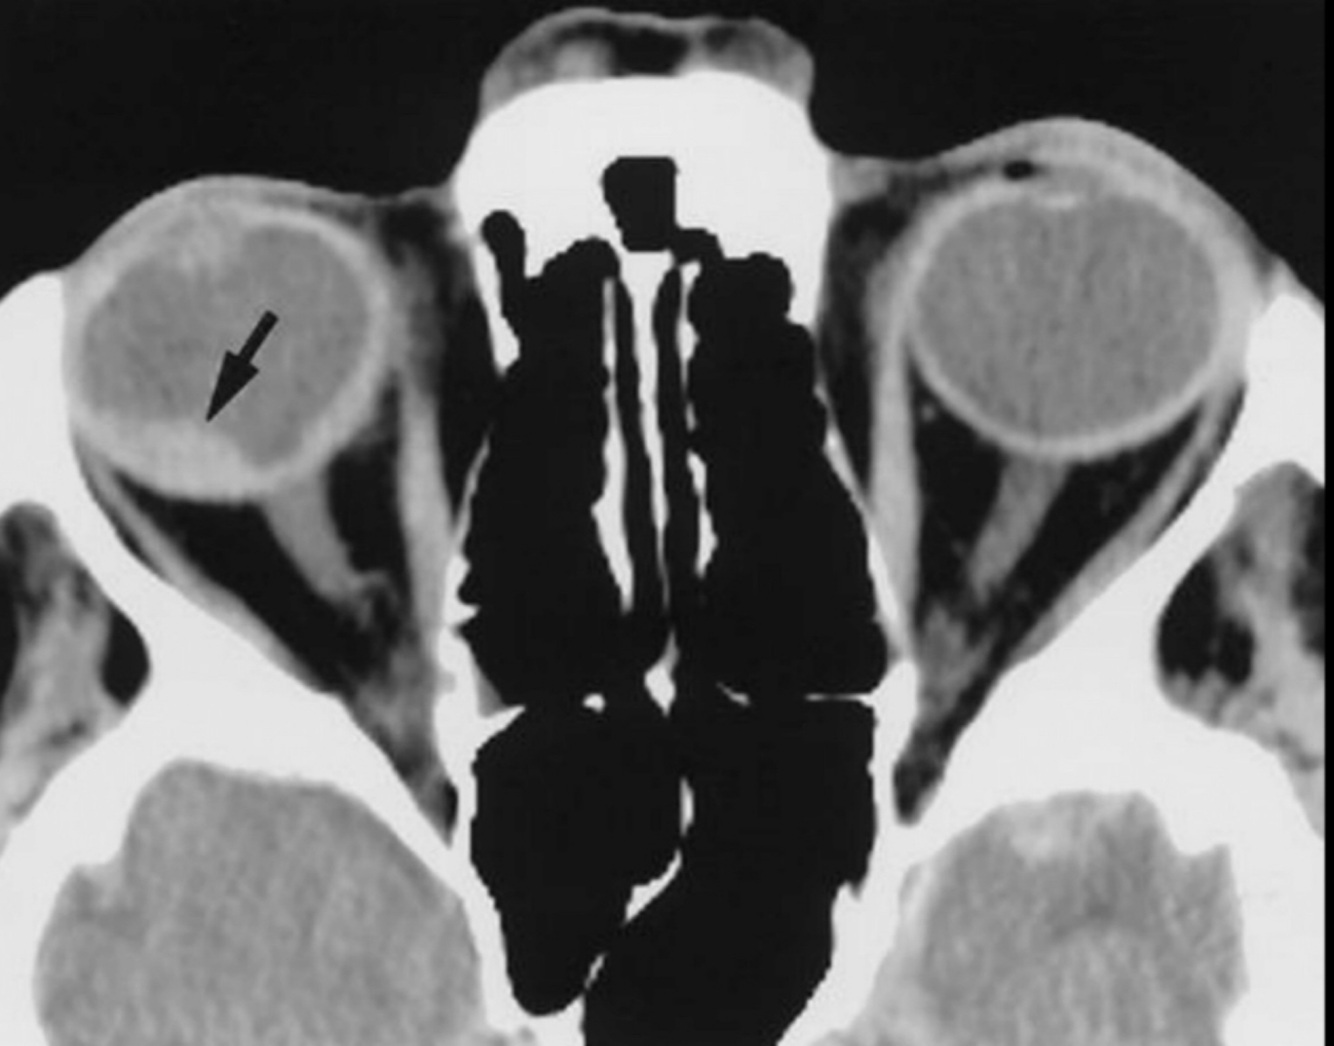

Hallazgos de TC de RB:

A

• Calcificación manchada o punteada

• Masa con densidad intermedia

• Capta contraste